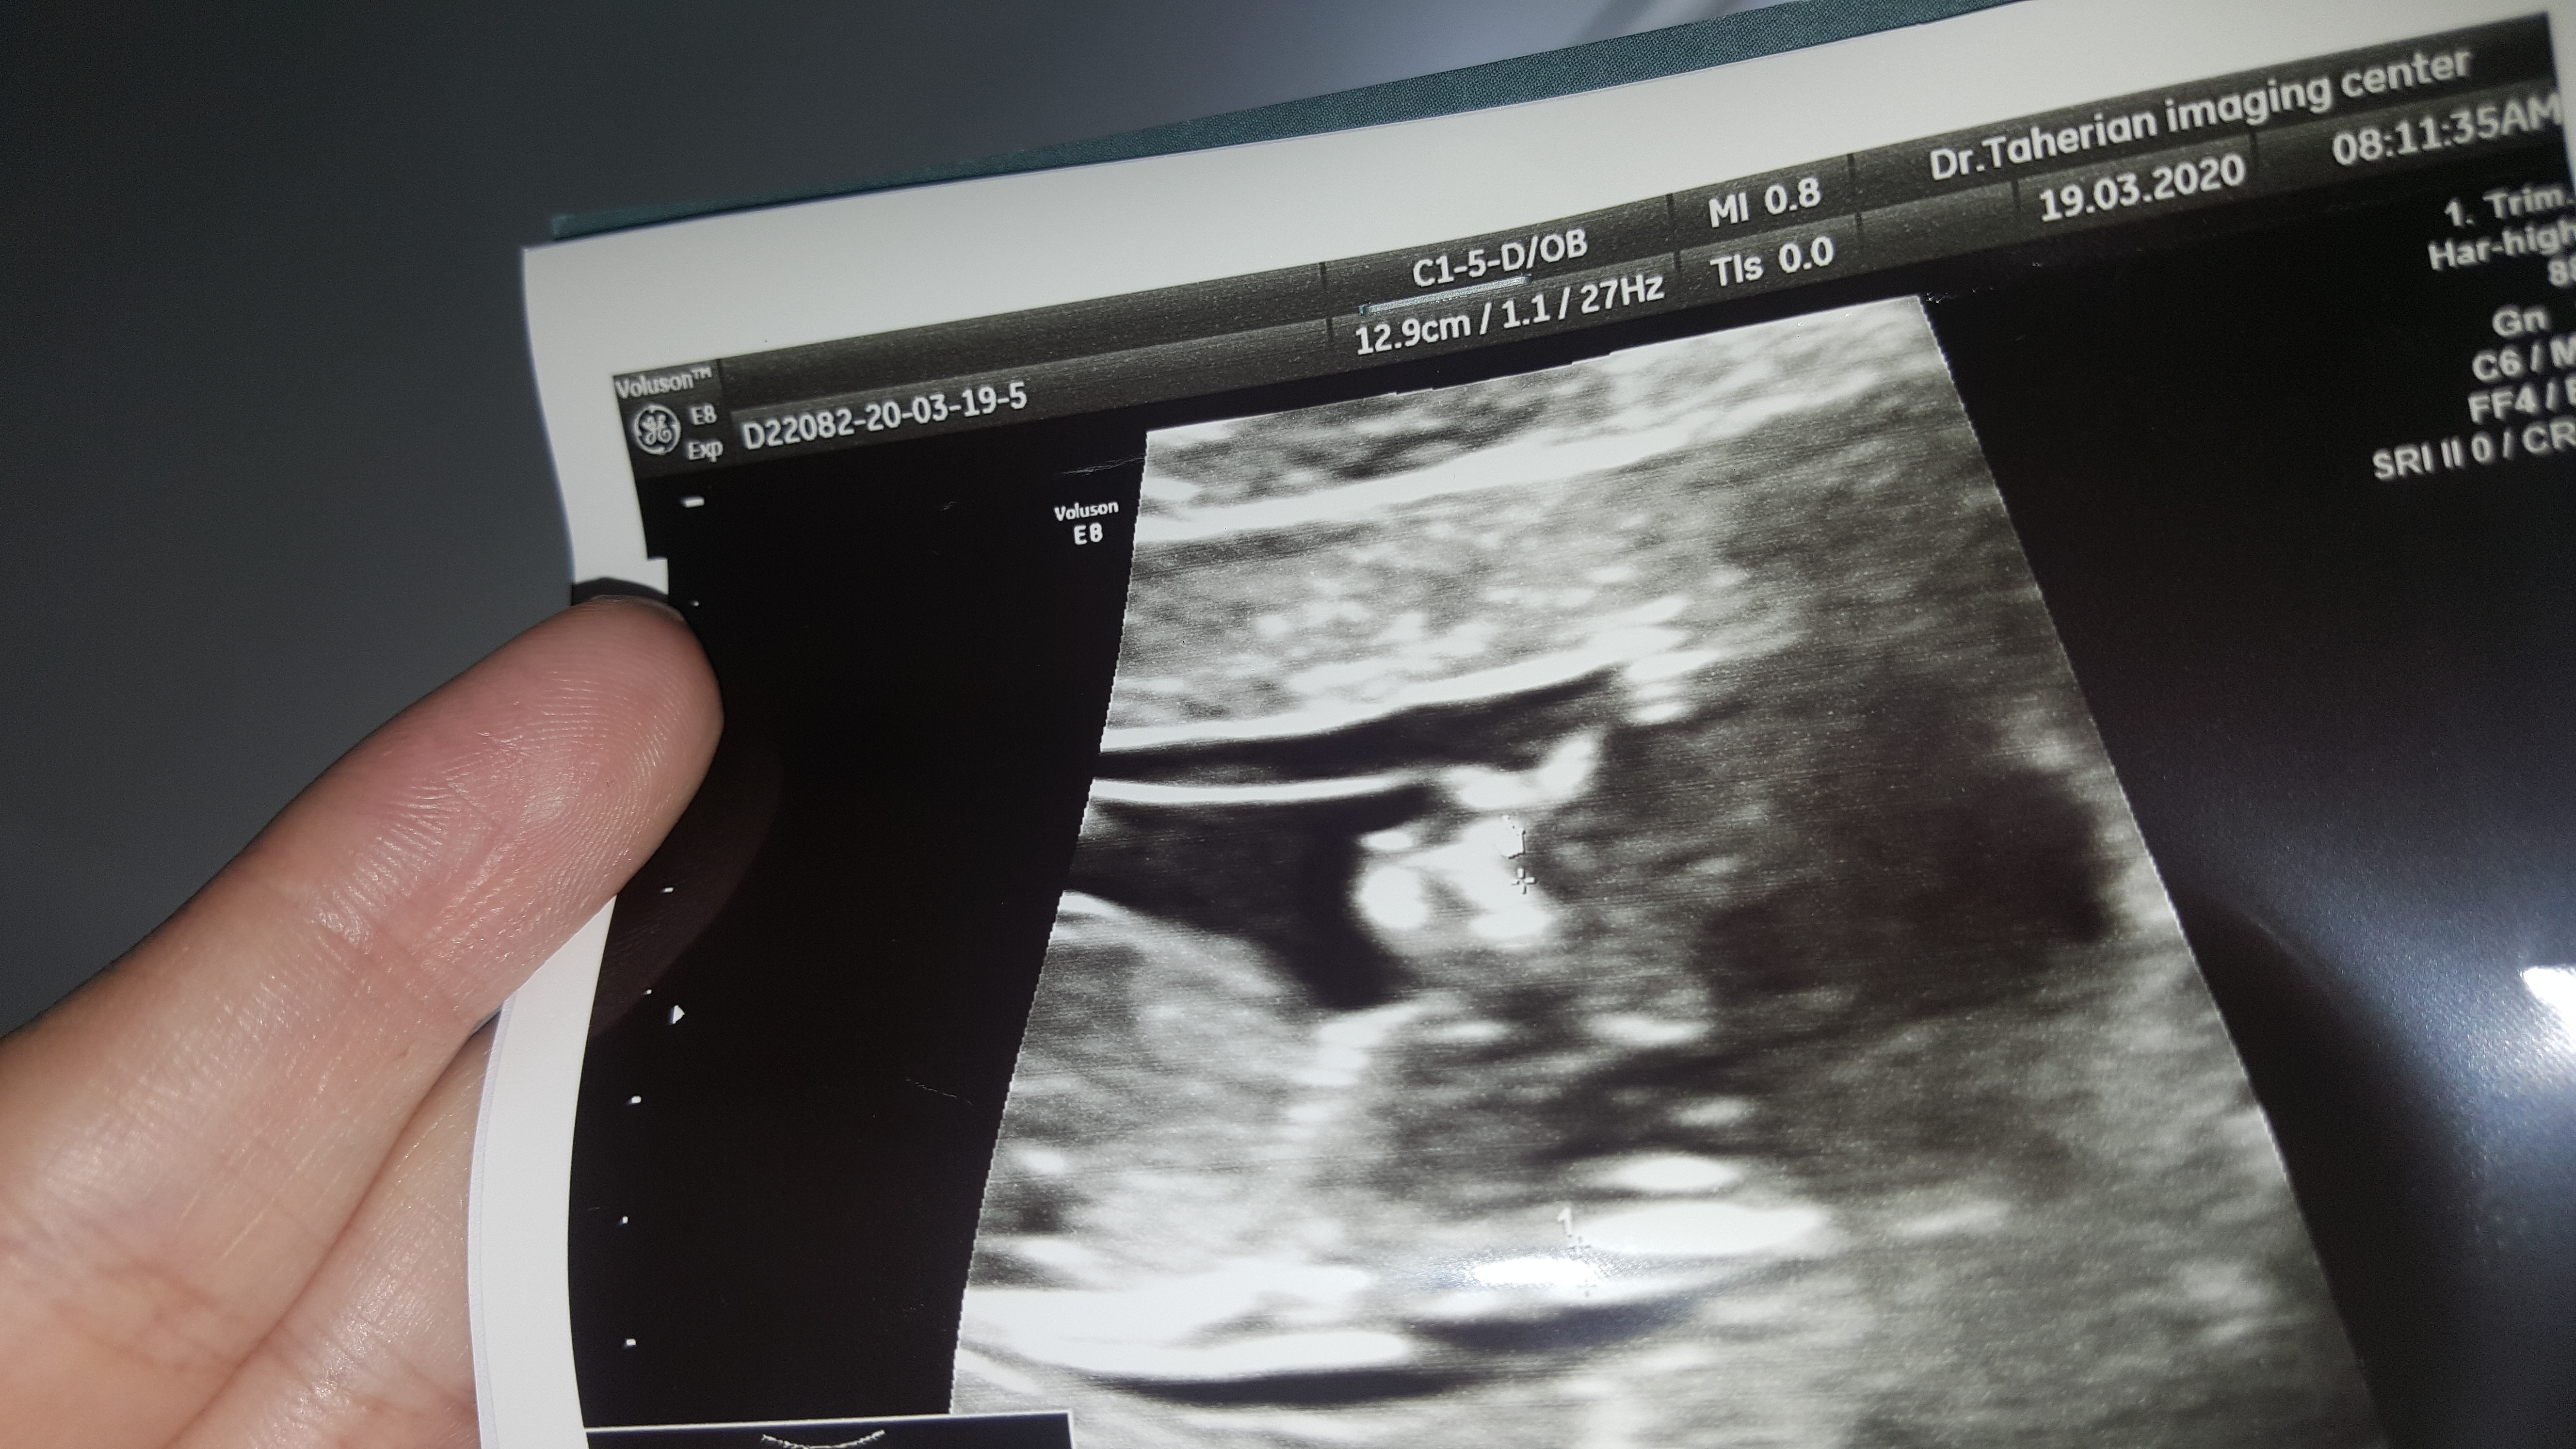

هستي96 مدیر عضویت: 1396/07/11 تعداد پست: 289 عنوان عکس سونوnt | مشاهده متن کامل بحث + 172 بازدید | 23 پست خانما میشه بیایین جنسیت نینیمواز رو عکس سونو غربالگری حدس بزنید ممنون هیچ وقت ب خودت مغرور نشو وبه کسی فخرفروشی نکن خدا حواسش ب همه کس و همه چیز هست.... 1400/03/27 | 12:38 0 نفر لایک کرده اند ... گزارش تاپیک نامناسب